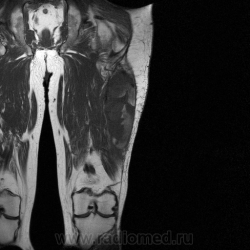

Добрый вечер Татьяна Валентиновна, можно и МРТ, а можно и результат гистологии, все по порядку, сейчас МРТ продемонстрирую.

Ну вот аксиальные срезы, где то затерял =(

С учетом вашего опыта, мне кажется Вам и без дословной интерпретации МР-протокола будет все понятно.

Мой коллега в заключении указал о вероятней всего рабдолейомиосаркоме, если я ошибся то чуть позже поправлюсь.

Я тоже пока что в этом деле лось, но думаю дело поправимое, на днях улетаю С-Петербуг в МАПО(цикл КТ и МРТ), ну да ладно, что косается пациента то он ещё в 2007 году обращался по месту жительства к травматологу по поводу ушиба бедра с формированием гематомы, была назначена местная рассасывающая терапия, до 2009г. видимо ждали пока рассасется в декабре обратился к хирургу по поводу посинения и увеличения в объёме задней поверхности бедра, назначен гепарин в феврале был вскрыт абсцесс в этом месте, далее только в марте сподхватились по УЗИ-мягких тканей признаки образования, ну и открытая ножевая биопсия: Описание изменений, выявленных при микроскопическом исследовании: в материале фрагменты опухоли, представленной пучками вытянутых клеток с полиморфными гиперхромными, местами уродливыми ядрами. Определяется значительное количество митозов, встречаются поля некроза опухоли. При иммуногистохимическом исследовании опухолевые клетки экспрессируют виментин, отсутствует реакция на десмин, гладко-мышечный актин, S100. Патоморфологическое заключение: саркома мягких тканей, боее вероятно фибросаркома.